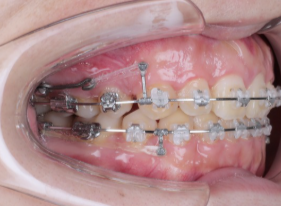

歯科矯正用アンカースクリューから前歯を引いている症例